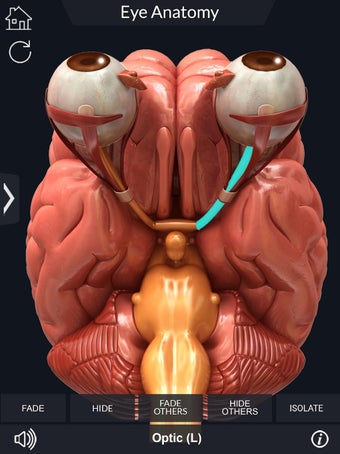

Изучите в деталях человеческий глаз и его анатомию с помощью этого простого в использовании бесплатного приложения для Android. Он позволяет масштабировать и вращать на 360° вокруг высокореалистичной 3D-модели глаза, а также рисовать на экране или прослушивать звуковое произношение каждого термина.

Вы можете выбрать X- просмотр луча, скрытие и отображение отдельных частей глаза, а также рисование или белый цвет на экране и обмен снимками экрана, звуковое произношение для всех анатомических терминов и многое другое.

Каждая часть разделена на отдельный вид, где вы можете можно увидеть название детали и ее расположение на глаз.